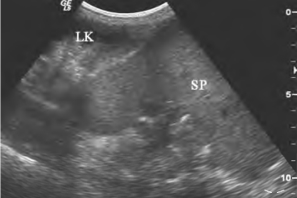

图24-7 游走脾脏声像图

位于盆腔LK:左肾;SP:脾脏